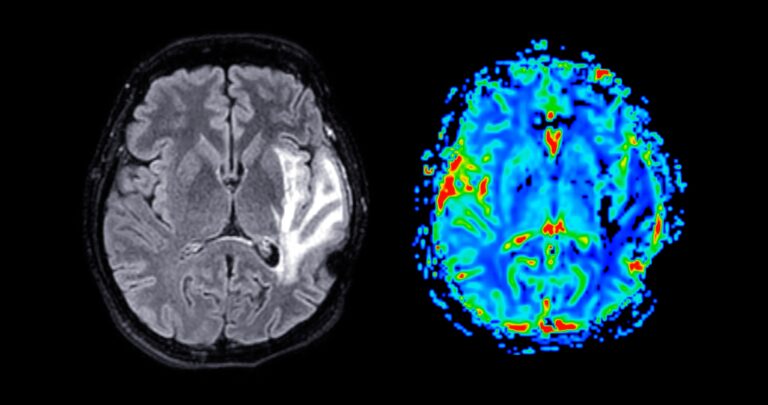

About one in 10 people in the UK aged 70 and over may have brain changes linked to Alzheimer’s disease, according to a large new population-based study.

The research, published in Nature, analysed blood samples from nearly 11,500 people and found that more than 1 million over-70s could meet NHS criteria for anti-amyloid treatment, far higher than current estimates. The findings are not a diagnosis but suggest many people carry early disease markers.

Experts say the study could improve early detection, though current treatments are expensive and not widely available on the NHS. The likelihood of Alzheimer’s-related brain changes rises sharply with age, reaching around two-thirds of people over 90.